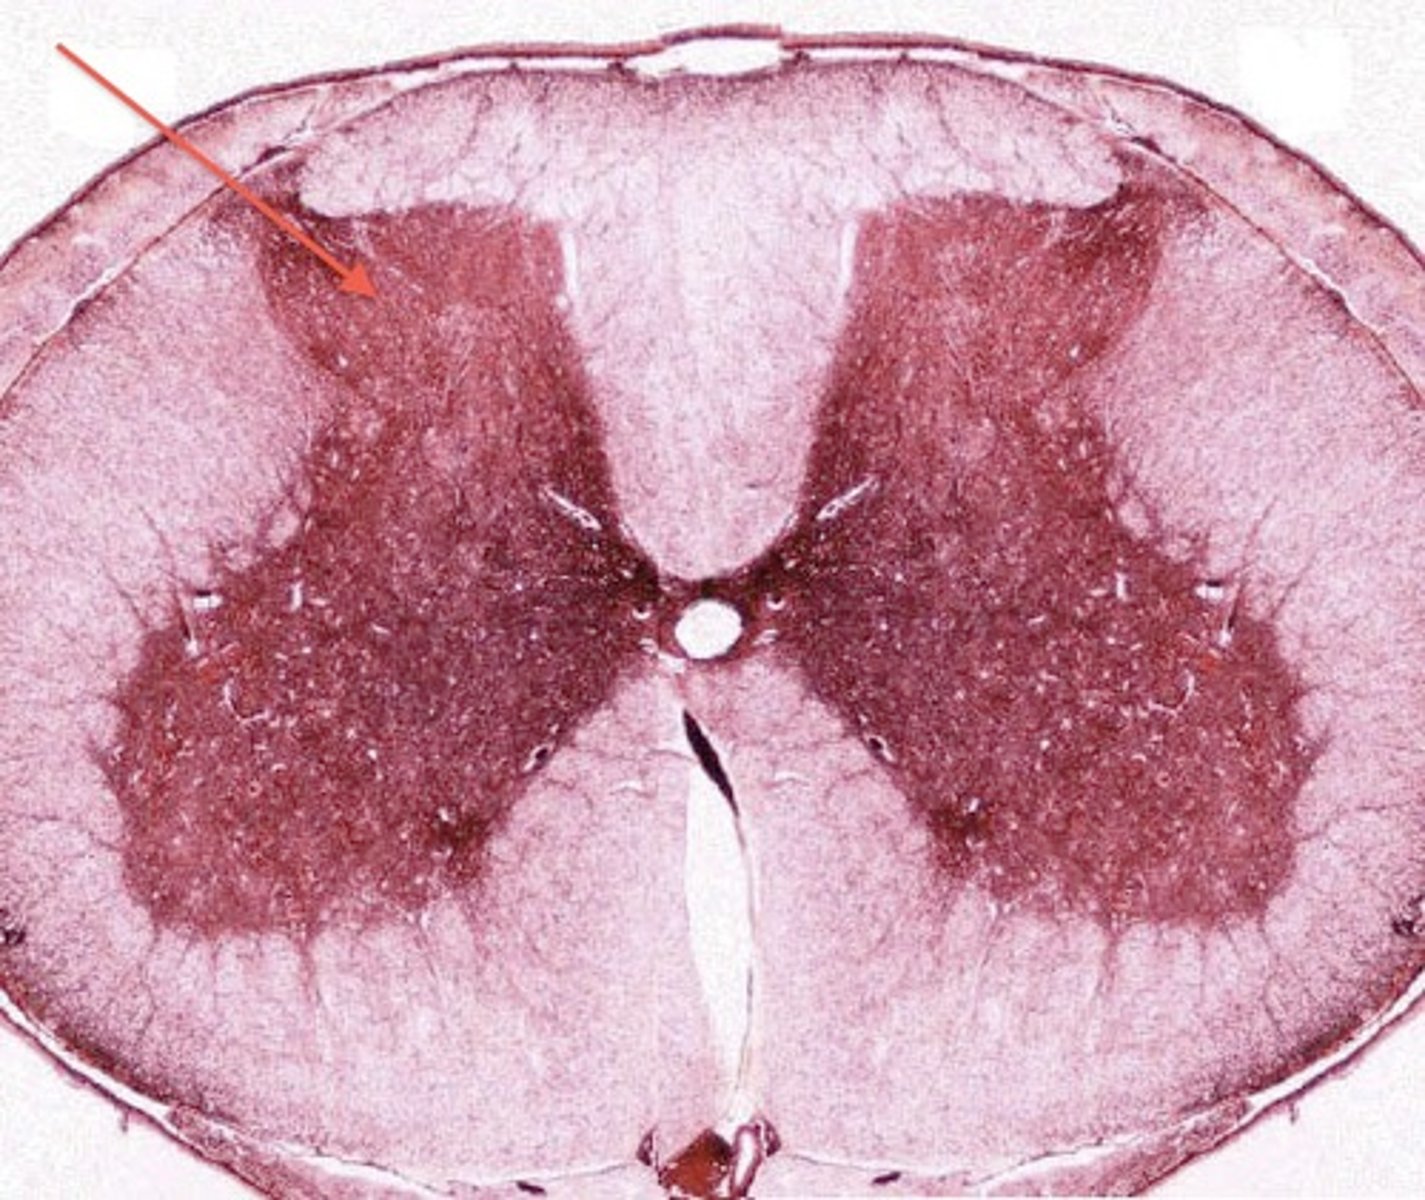

grey matter

(in orange)

dorsal horn

lateral horn

ventral horn

dorsal median sulcus

ventral median fissure

grey commissure

central canal

white matter

dorsal column

lateral column

ventral column